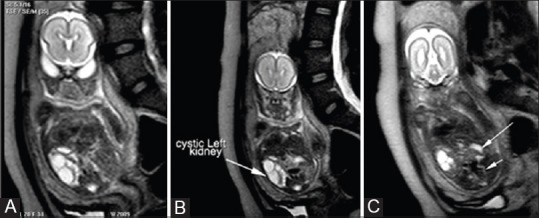

![]() Značný oligohydramniom s agenezi pravý ledviny a moč. měchýřu | |

Oligohydramnion je snížené množství plodové vody. Vyskytuje se nejčastěji při ruptuře vaku blan, dále při placentární insuficienci, vývojových vadách ledvin (ageneze, hypoplázie), vývojových vadách vývodných cest močových, odchylkách karyotypu a závažných srdečních chorobách Sonograficky oligohydramnion je definovaný pod AFI 5. [1].